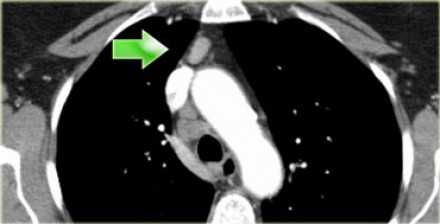

Лимфатические узлы 3 группы не примыкают к трахее в отличии от лимфатических узлов 2 группы. Они подразделюятся на: 3А кпереди от сосудов 3Р позади пищевода/превертебрально Они не доступны при медиастиноскопии. 3Р группа может быть доступна при чреспищеводной эхокардиографии.

На изображении слева 3А узел в преваскулярном пространстве. Обратите внимание так же на ниже расположенные паратрахеальные узлы справа относящиеся к 4R группе.

3. Преваскулярные и ретротрахеальные: кпереди от сосудов (3А) и превертебральные (3Р)